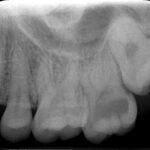

画像の矢印部分ですが少し黒いのみで大きな虫歯に

見えません。

しかしレントゲンを見ますと中がかなり虫歯になっています。

黒い部分が虫歯です。